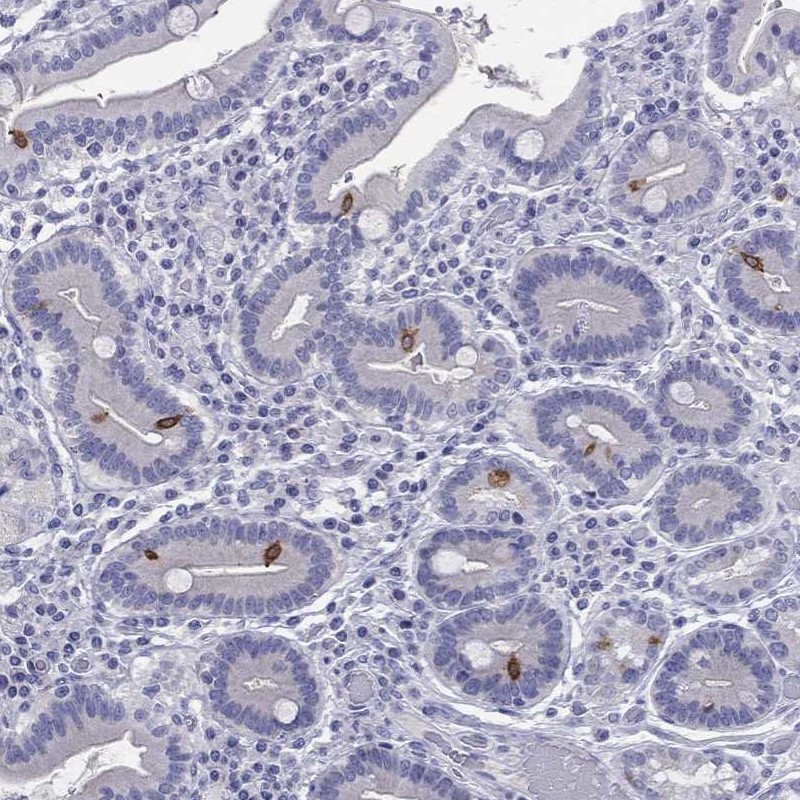

Immunohistochemical staining of human duodenum shows strong cytoplasmic positivity in glandular cells.